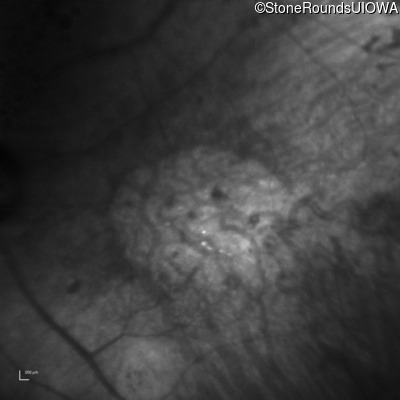

Infrared Fundus Photograph - Left - 1/200 sc

Exemplar